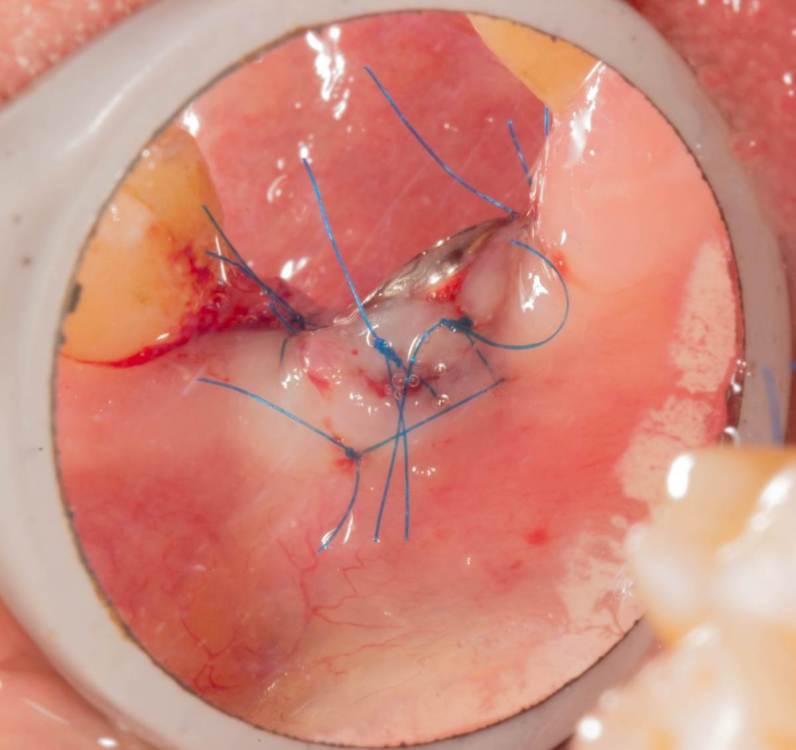

Женька Опубликовано 19 июня, 2023 Поделиться Опубликовано 19 июня, 2023 Здравствуйте, коллеги. Примерно с нового года начал ставить ТЛ имплантаты Дентиум. Что-то под заглушку (не поймал торки, представляете?). Что-то на низких формирвателях. И вот пришла пора протезирования, но отпустить к ортопеду не подготовив десну - не получается. Создал сам себе проблем, сегодня вот исправлял. Получилось неплохо? 3 Ссылка на комментарий

Женька Опубликовано 20 июня, 2023 Автор Поделиться Опубликовано 20 июня, 2023 @АнтонТЛТ мы же позиционируем платформу относительно зенита? Есть ли разница тогда, какой имплантат мы выбираем? Вообще весь смысл здесь был заложен в том, что толщина гребня была не очень. Хотелось поставить тонкий имплантат 3.6. Но рисковать тонкой платформой не хотелось, поэтому выбор пал на 4.8 платформу ТЛ и тело имплантата 3.6 1 Ссылка на комментарий